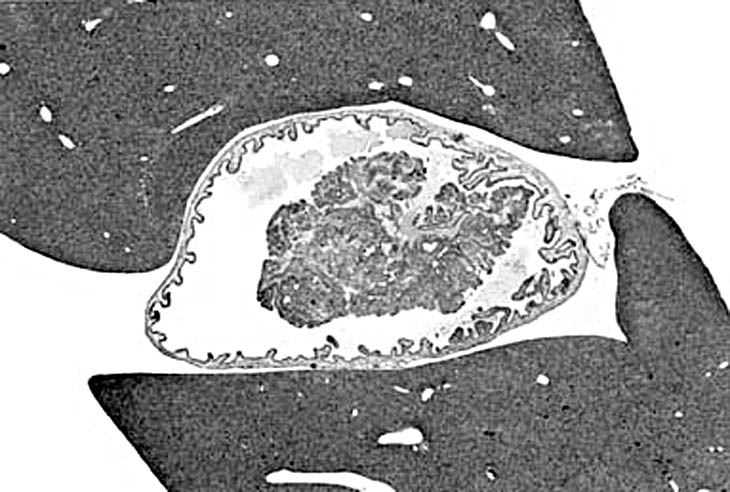

A papillary adenoma of the gallbladder in an adult mouse. Higher magnification reveals multiple layers of proliferating epithelium lining a connective tissue stalk.